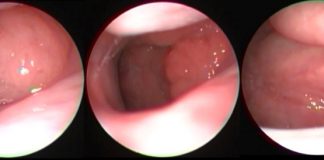

Çocuklarda Endoskopik Geniz Eti Muayenesi

Geniz Eti - Adenoid

Op. Dr. Atilla Şengör